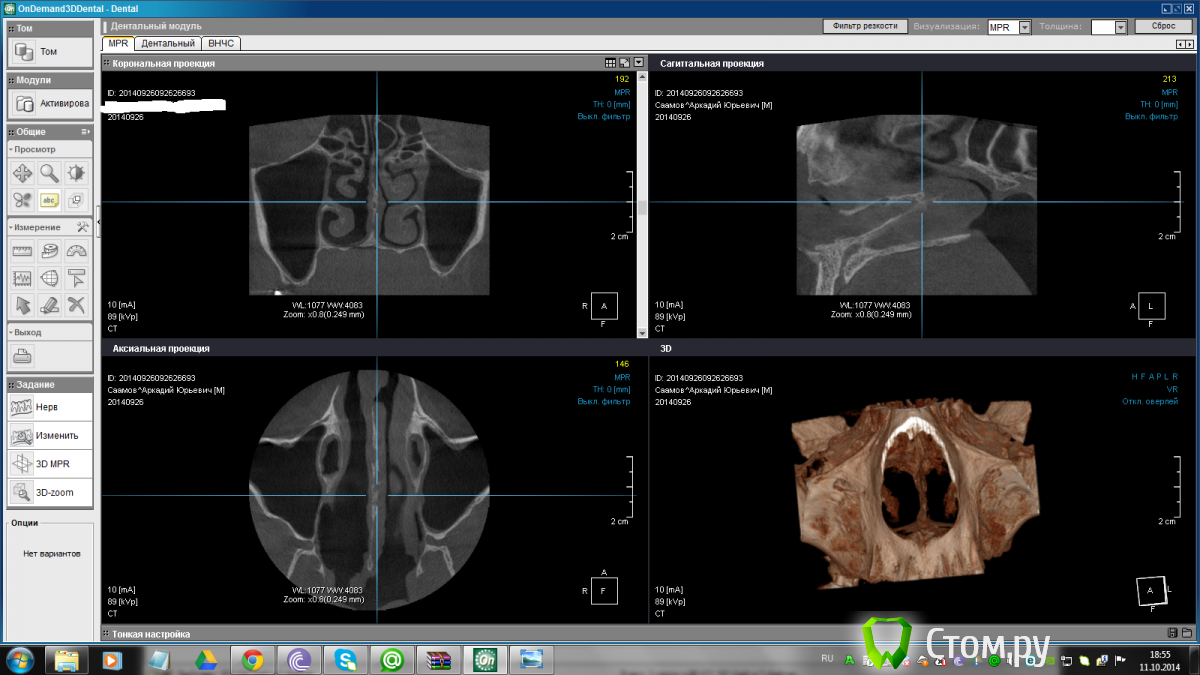

TIGER Опубликовано 4 октября, 2014 Поделиться Опубликовано 4 октября, 2014 Коллеги подскажите какой вид аугментации предпочтителен,при такой СКОРЛУПЕ помимо синус лифта?(Пациент пока отправлен к ЛОРУ на санацию) Ссылка на комментарий

TIGER Опубликовано 4 октября, 2014 Автор Поделиться Опубликовано 4 октября, 2014 А что там со слизистой? Где она заканчивается?По кт весь просвет заполняет Ссылка на комментарий

TIGER Опубликовано 11 октября, 2014 Автор Поделиться Опубликовано 11 октября, 2014 Значит отправил пациента на КТ пазух,а там другая картина.....чисто)Как так?Назначил на синус_лифт пока Ссылка на комментарий

TIGER Опубликовано 11 октября, 2014 Автор Поделиться Опубликовано 11 октября, 2014 А это точно тот же самый пациент и срез там же, где и в первом посте?Чем это лор так полечил вашего пациента что снимки так сильно изменились?)) Вы знаете сам не могу понять!!!Отправил первый срез ЛОРУ,он говорит сделайте КТ пазух отдельно,вчера сделал,получил диск открыл и был в шоке....))Недоумеваю,может это загадки КТ? Ссылка на комментарий

stommm Опубликовано 11 октября, 2014 Поделиться Опубликовано 11 октября, 2014 Может диск другого пациента прислали? На первом срезе есть нарушение целостности латеральной стенки (поправьте если не прав). На втором кт это есть? Ссылка на комментарий

TIGER Опубликовано 12 октября, 2014 Автор Поделиться Опубликовано 12 октября, 2014 Может диск другого пациента прислали? На первом срезе есть нарушение целостности латеральной стенки (поправьте если не прав). На втором кт это есть?Есть...проверил) Ссылка на комментарий

TIGER Опубликовано 13 октября, 2014 Автор Поделиться Опубликовано 13 октября, 2014 пациент сегодня сказал,что неделю назад был у него насморк) Ссылка на комментарий

andr99 Опубликовано 13 октября, 2014 Поделиться Опубликовано 13 октября, 2014 У двоих моих пациентов так было.На КТ полное заполнение пазухи. Отправлял к ЛОРам. Через две недели - все чисто. На антибиотиках и назальных спреях, говорят, выводили. Ссылка на комментарий